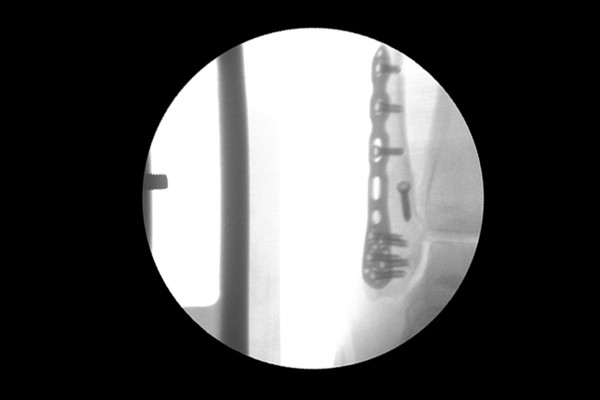

수술은 실시간 X-RAY인 C-ARM을 보면서 진행하였고, 먼저 바깥쪽 복숭아뼈를 금속판(플레이트)과 지연나사(lag screw)로 고정합니다.

96707d45bfa78bc815f4e3f85a28a525_1757921671_4984.jpg

골절편이 작은 안쪽 복숭아뼈(내복사)는 작은 스크류와 핀, 와이어로 고정해줍니다.